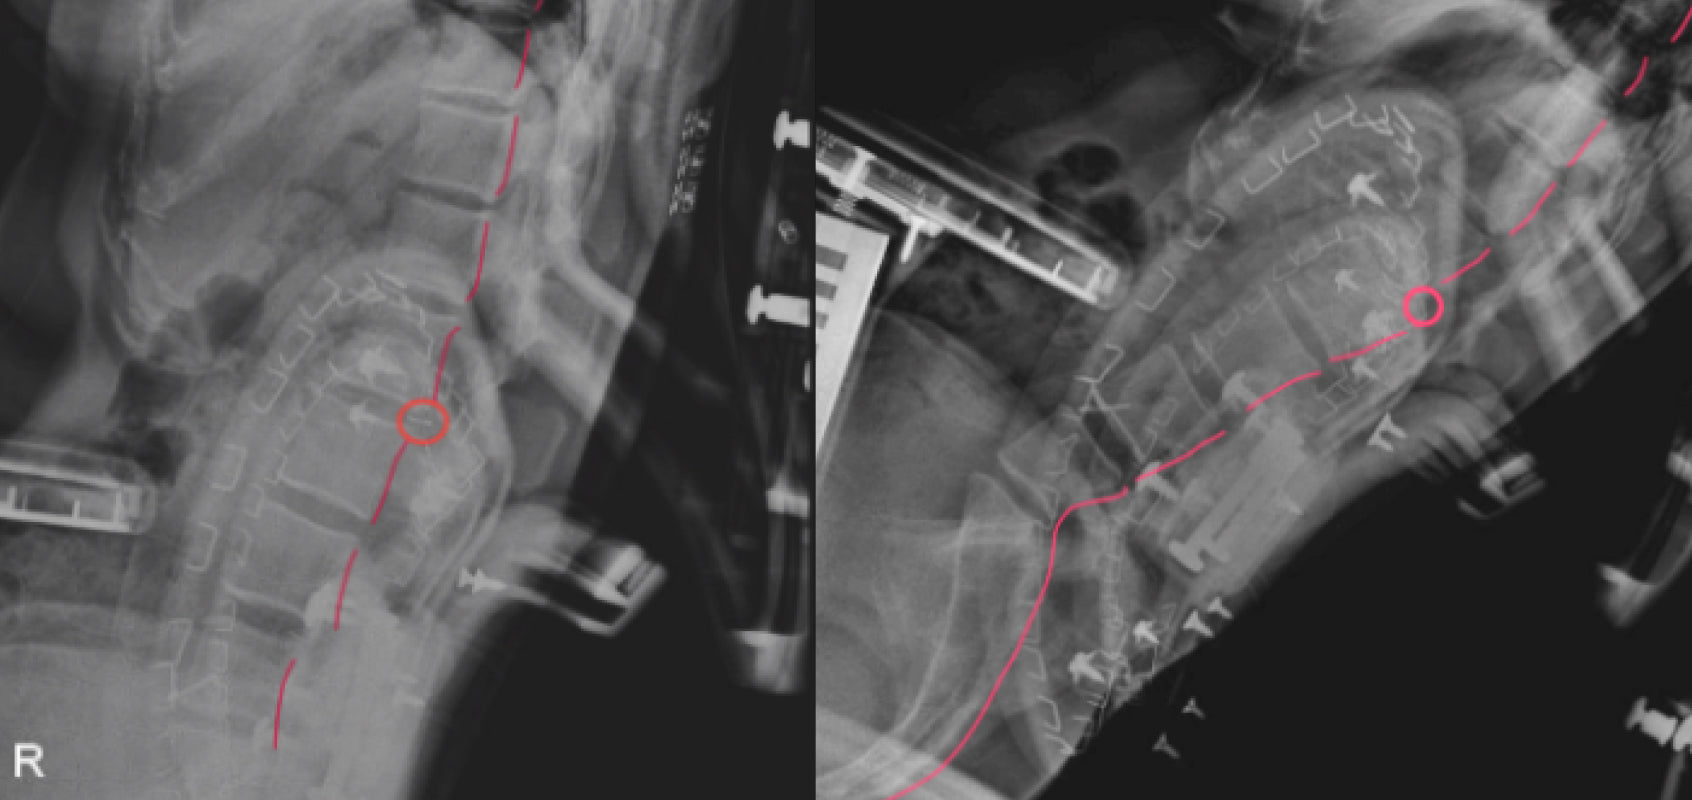

Spinal Biomechanics: The human body is remarkably complex, and a chair’s backrest must reflect the intricacies of our skeletal structure. The spine is a continuous system—supporting just one section can disrupt overall alignment. What’s more, every individual has a unique spinal curve, making personalized support essential for true ergonomic comfort.

We’ve also found that chairs with pronounced lumbar protrusions can actually disrupt the spine’s natural curve, as shown in X-ray imaging. This leads to unnatural breaks in spinal alignment and increases pressure on specific segments of the spine.

*Source: LiberNovo Internal Laboratory